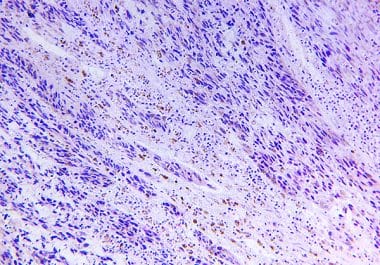

The FDA approved a kinase inhibitor for the treatment of inflammatory myofibroblastic tumors in children and adults. The U.S....